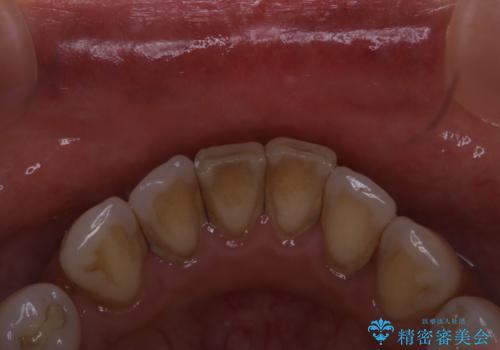

全体の総合的な治療前にPMTC

- 歯科がだいぶ久しぶりで、全額的な治療の前にクリーニングを希望されました。PMTC60分コースを行いました。

歯にステイン(着色)や歯石などが付着していると、汚れなのか虫歯なのかの判別が分かりにくく、正確な診断ができないことがあります。

そのため、治療前には専門的な機械や材料を使用したクリーニング(PMTC)をすることで、ご自身本来の歯の状態となります。より、精密な治療前を行うためには、治療前などにPMTCを行いお口の中の環境を綺麗にすることがおすすめです。